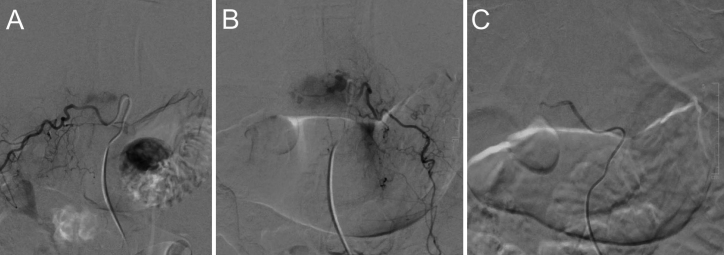

Observations: This report details a unique case of thoracic PMHE in a 60-year-old woman managed with a multistaged surgical approach, including preoperative embolization and en bloc spondylectomy. The authors describe the patient's clinical presentation, radiographic findings, surgical technique, and postoperative course, highlighting the role of en bloc resection in achieving tumor control.